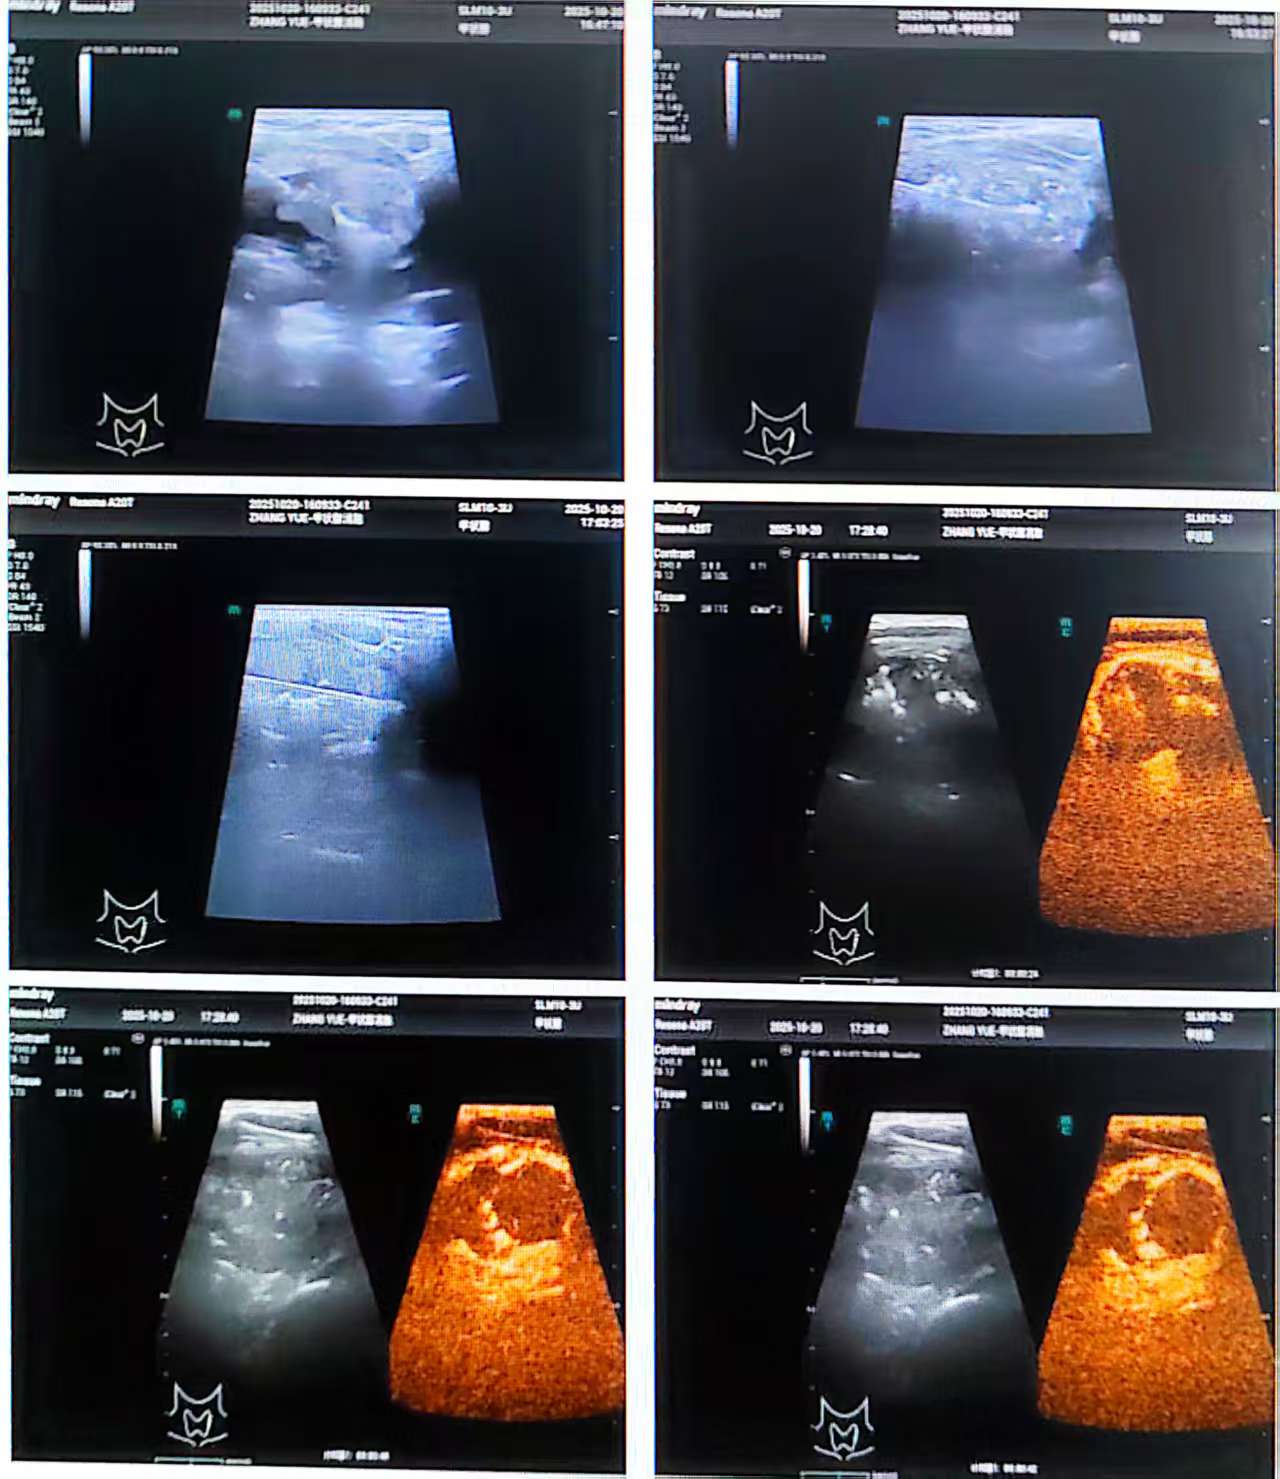

阳光讯(记者 郑亚雷 通讯员 张兰兰 张永东 王杰)近日,西安大兴医院渭水园院区内分泌代谢科、超声介入科、病理科三科联手,首次引入并开展了甲状腺快速染色技术(ROSE)。该技术实现了甲状腺病灶手术床旁即时病理诊断,结合先进微创治疗手段,大幅优化诊疗流程,为甲状腺结节患者提供了高效、精准、微创的诊疗服务。

为破解这一困境, 内分泌代谢科王杰主任团队采用前沿的“诊疗一体化”方案。术中,通过快速现场评估(ROSE)技术,病理诊断时间从“5天”缩短至“几分钟”,为后续治疗提供了即时决策依据。

张永东主任启动多学科协作(MDT)诊疗流程,邀请病理科杨巧医生共同会诊。在超声引导下,张主任精准完成穿刺取样,杨巧医生随即运用 ROSE 技术,于手术床旁即刻完成细胞学诊断,确认结节为良性。

科普:诊断性现场快速评估(Rapid On-Site Evaluation,ROSE)

ROSE是在细胞学检查中广泛应用的技术

√优势:微创、快速。染色2分钟,5分钟现场告知结果

√主要作用:在活检或穿刺过程中快速明确标本的质量和初步判断良恶性

技术核心:把病理科“搬”到手术床旁

传统病理诊断流程复杂、耗时较长,患者往往需要在手术中等待数日才能获得明确结果。而现在,借助全新的快速染色技术,医生在手术中获取组织样本后,仅需数分钟,即可在手术床旁完成制片、染色和判读,当场明确病变性质。